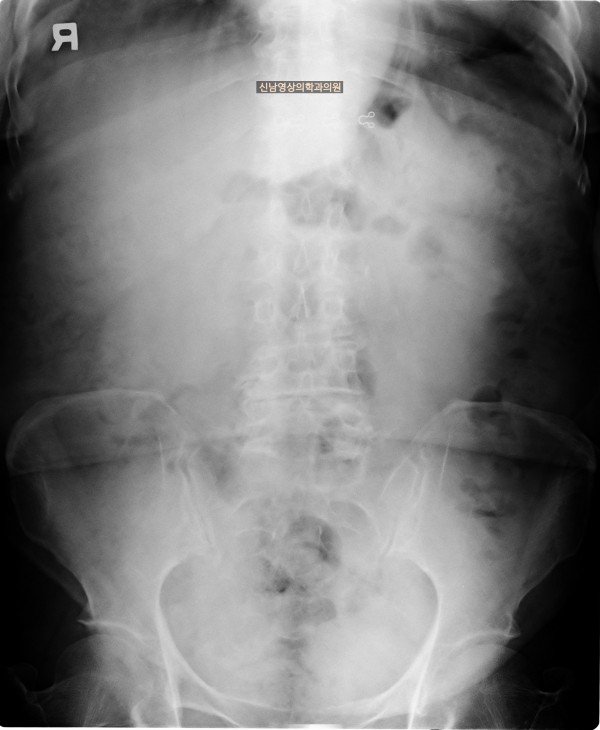

본 환자분은 변비가 지속되면서 좌하복부 통증이 있으셨던 분으로 본원에서 복부 초음파 검사를 진행하였습니다.

하행 결장 부위에서 장이 두꺼워진 소견이 보여 진행된 대장암의 가능성이 농후해보여 대학병원으로 전원해 대장내시경을 받고, 수술로 2기암으로 진단되신 케이스입니다.

위암이나 대장암은 점막에서 발생하는 0기암은 초음파로 진단할 수 없지만 대장암이 점막을 넘어 근육층이나 장간막으로 퍼지게 되면 초음파 검사상 근육, 장간막 부위가 두꺼워지는 소견으로 나타나 발견하기도 합니다.